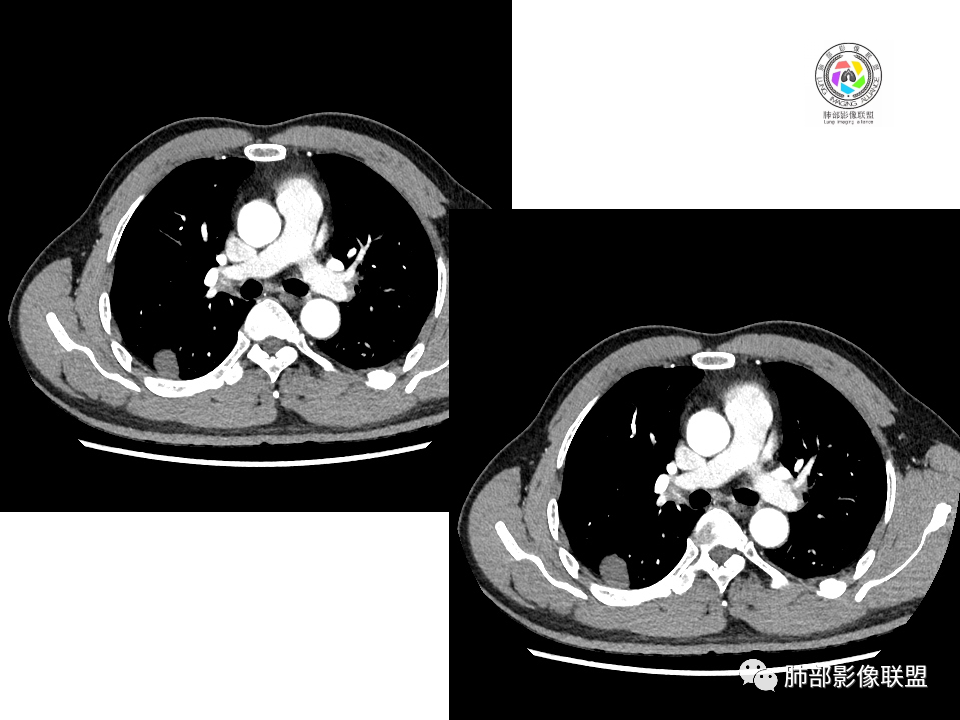

2.右肺下叶背段胸膜下块影,边界清楚光整,上下极见磨玻璃晕,未见明显分叶毛刺和棘状突起,未见胸膜凹陷或胸壁侵入。密度均匀,轻度不均匀强化。未见支气管进入。

1.边缘光整干净,大病灶缺乏坏死等,不符合鳞癌影像学特征。尽管有吸烟史,还是偏年轻。

2.边缘光整,会是小细胞癌或是大细胞癌吗?小细胞癌的肺门纵隔淋巴结增大往往十分夸张,该患者不符合。

注意,基底段支气管血管束旁的小结节影,即便是淋巴结,也与背段病灶引流途径不符。

3.会是转移瘤吗?如前所述,患者偏年轻,缺乏相关原发肿瘤病史,强化程度不高,似乎也缺乏支持点。

4.良性占位绕不过去,如发生于该部位的孤立性纤维瘤等……

病灶不均匀强化可以将含液支气管囊肿排除在外。